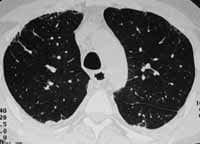

La tomografía axial computarizada de alta resolución ha contribuido de una manera especial al diagnóstico específico de esta entidad, a su reconocimiento más temprano y al seguimiento de los pacientes, determinando claramente cómo se va perdiendo el flujo sanguíneo pulmonar como consecuencia de la destrucción del parenquima (Fig. 5).

Figura 5. Enfisema centroacinar.